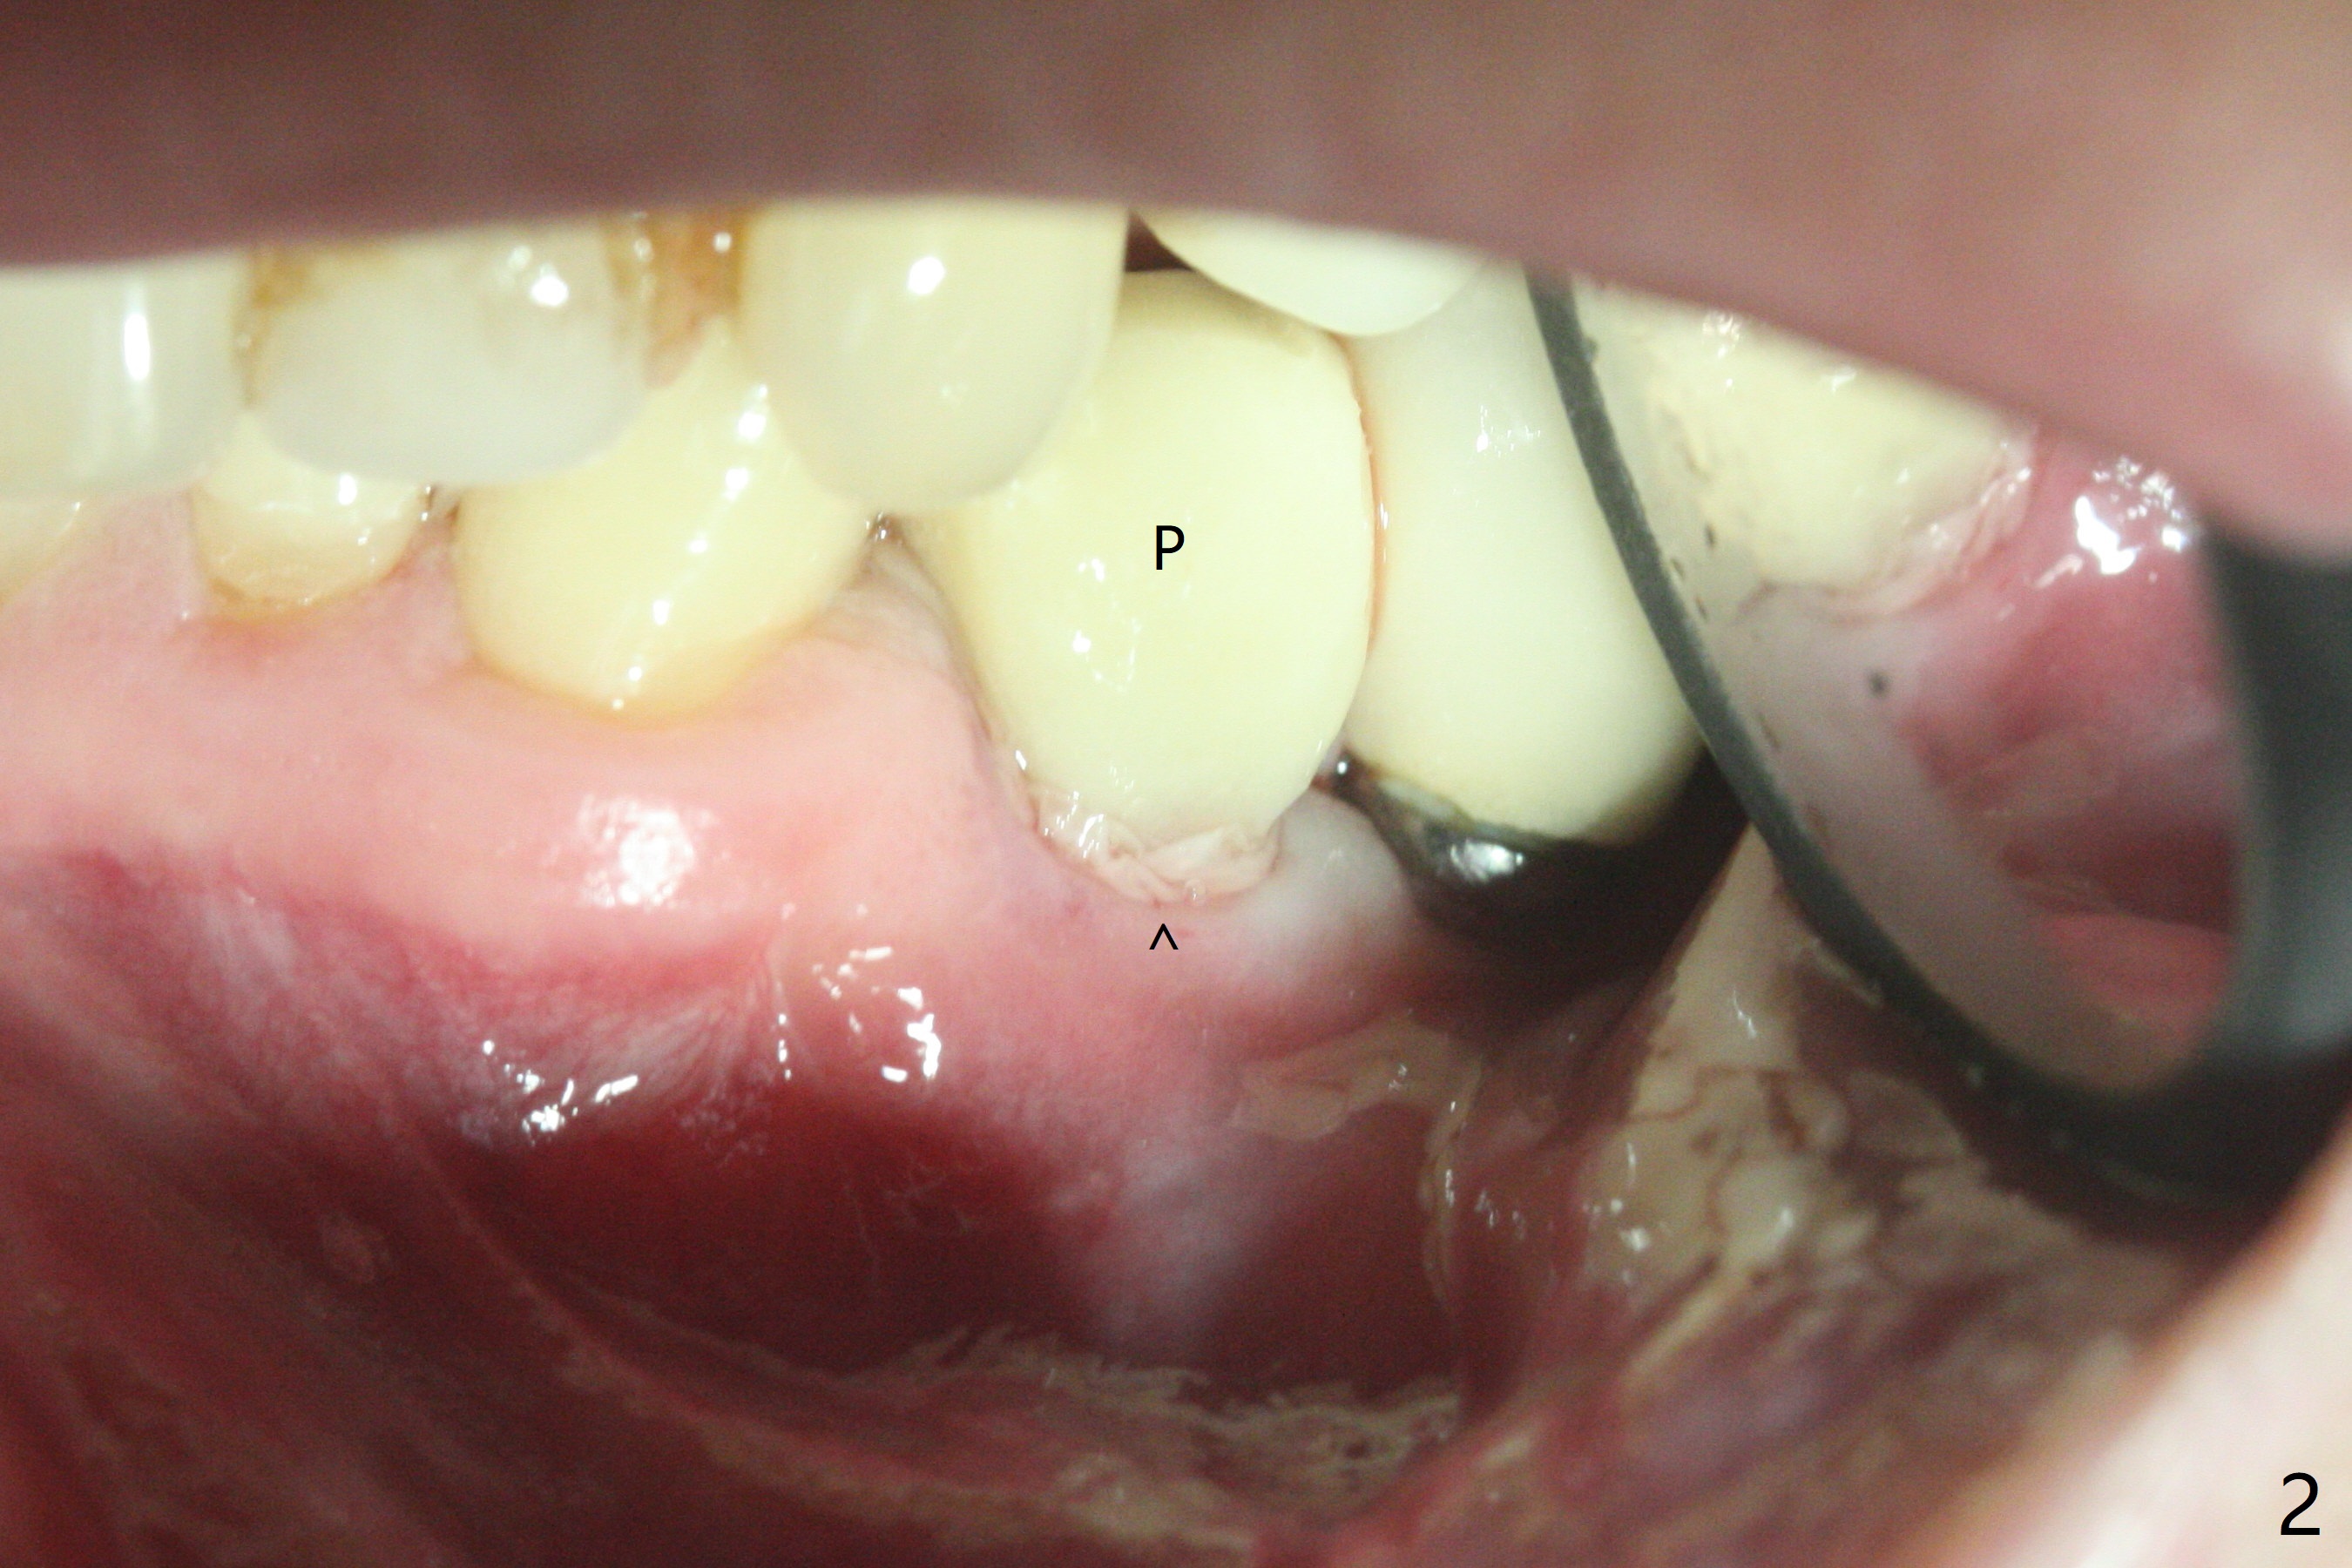

尽管使用导板,钻洞也不快,左下4植体仍旧偏移远中(图一)和颊侧(颊侧间隙比预计小),原因:斜面(图一:箭头),骨质硬,周围牙冠射线折射,导板就位前必须磨第二前磨牙近中面(今后遇到这些情景,选择徒手种植)。庆幸的是牙槽嵴水平两个植体还不是最接近(与根尖相比),粘性植骨(图一:*)但愿能缓解术后骨质吸收。制作临时牙冠后(图二:P),将PRF(图二:^;三:L(舌侧))插入牙冠和骨粉之间。术后六天软组织愈合正常(图四)。术后4个月远中牙槽嵴稍微下降(图五:*)。由于基台偏向远中,为了防止牙冠基台重新插入困难,基台不取出,先拧紧(20Ncm),牙冠口内粘固。